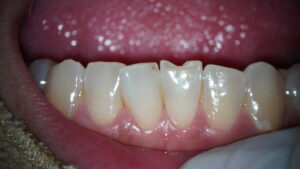

医院ブログ 2026/03/08

【表参道 歯科 ダイレクトボンディング】 破折した... こんにちは。表参道・青山にある歯科石上医院です。 自転車の交通事故…